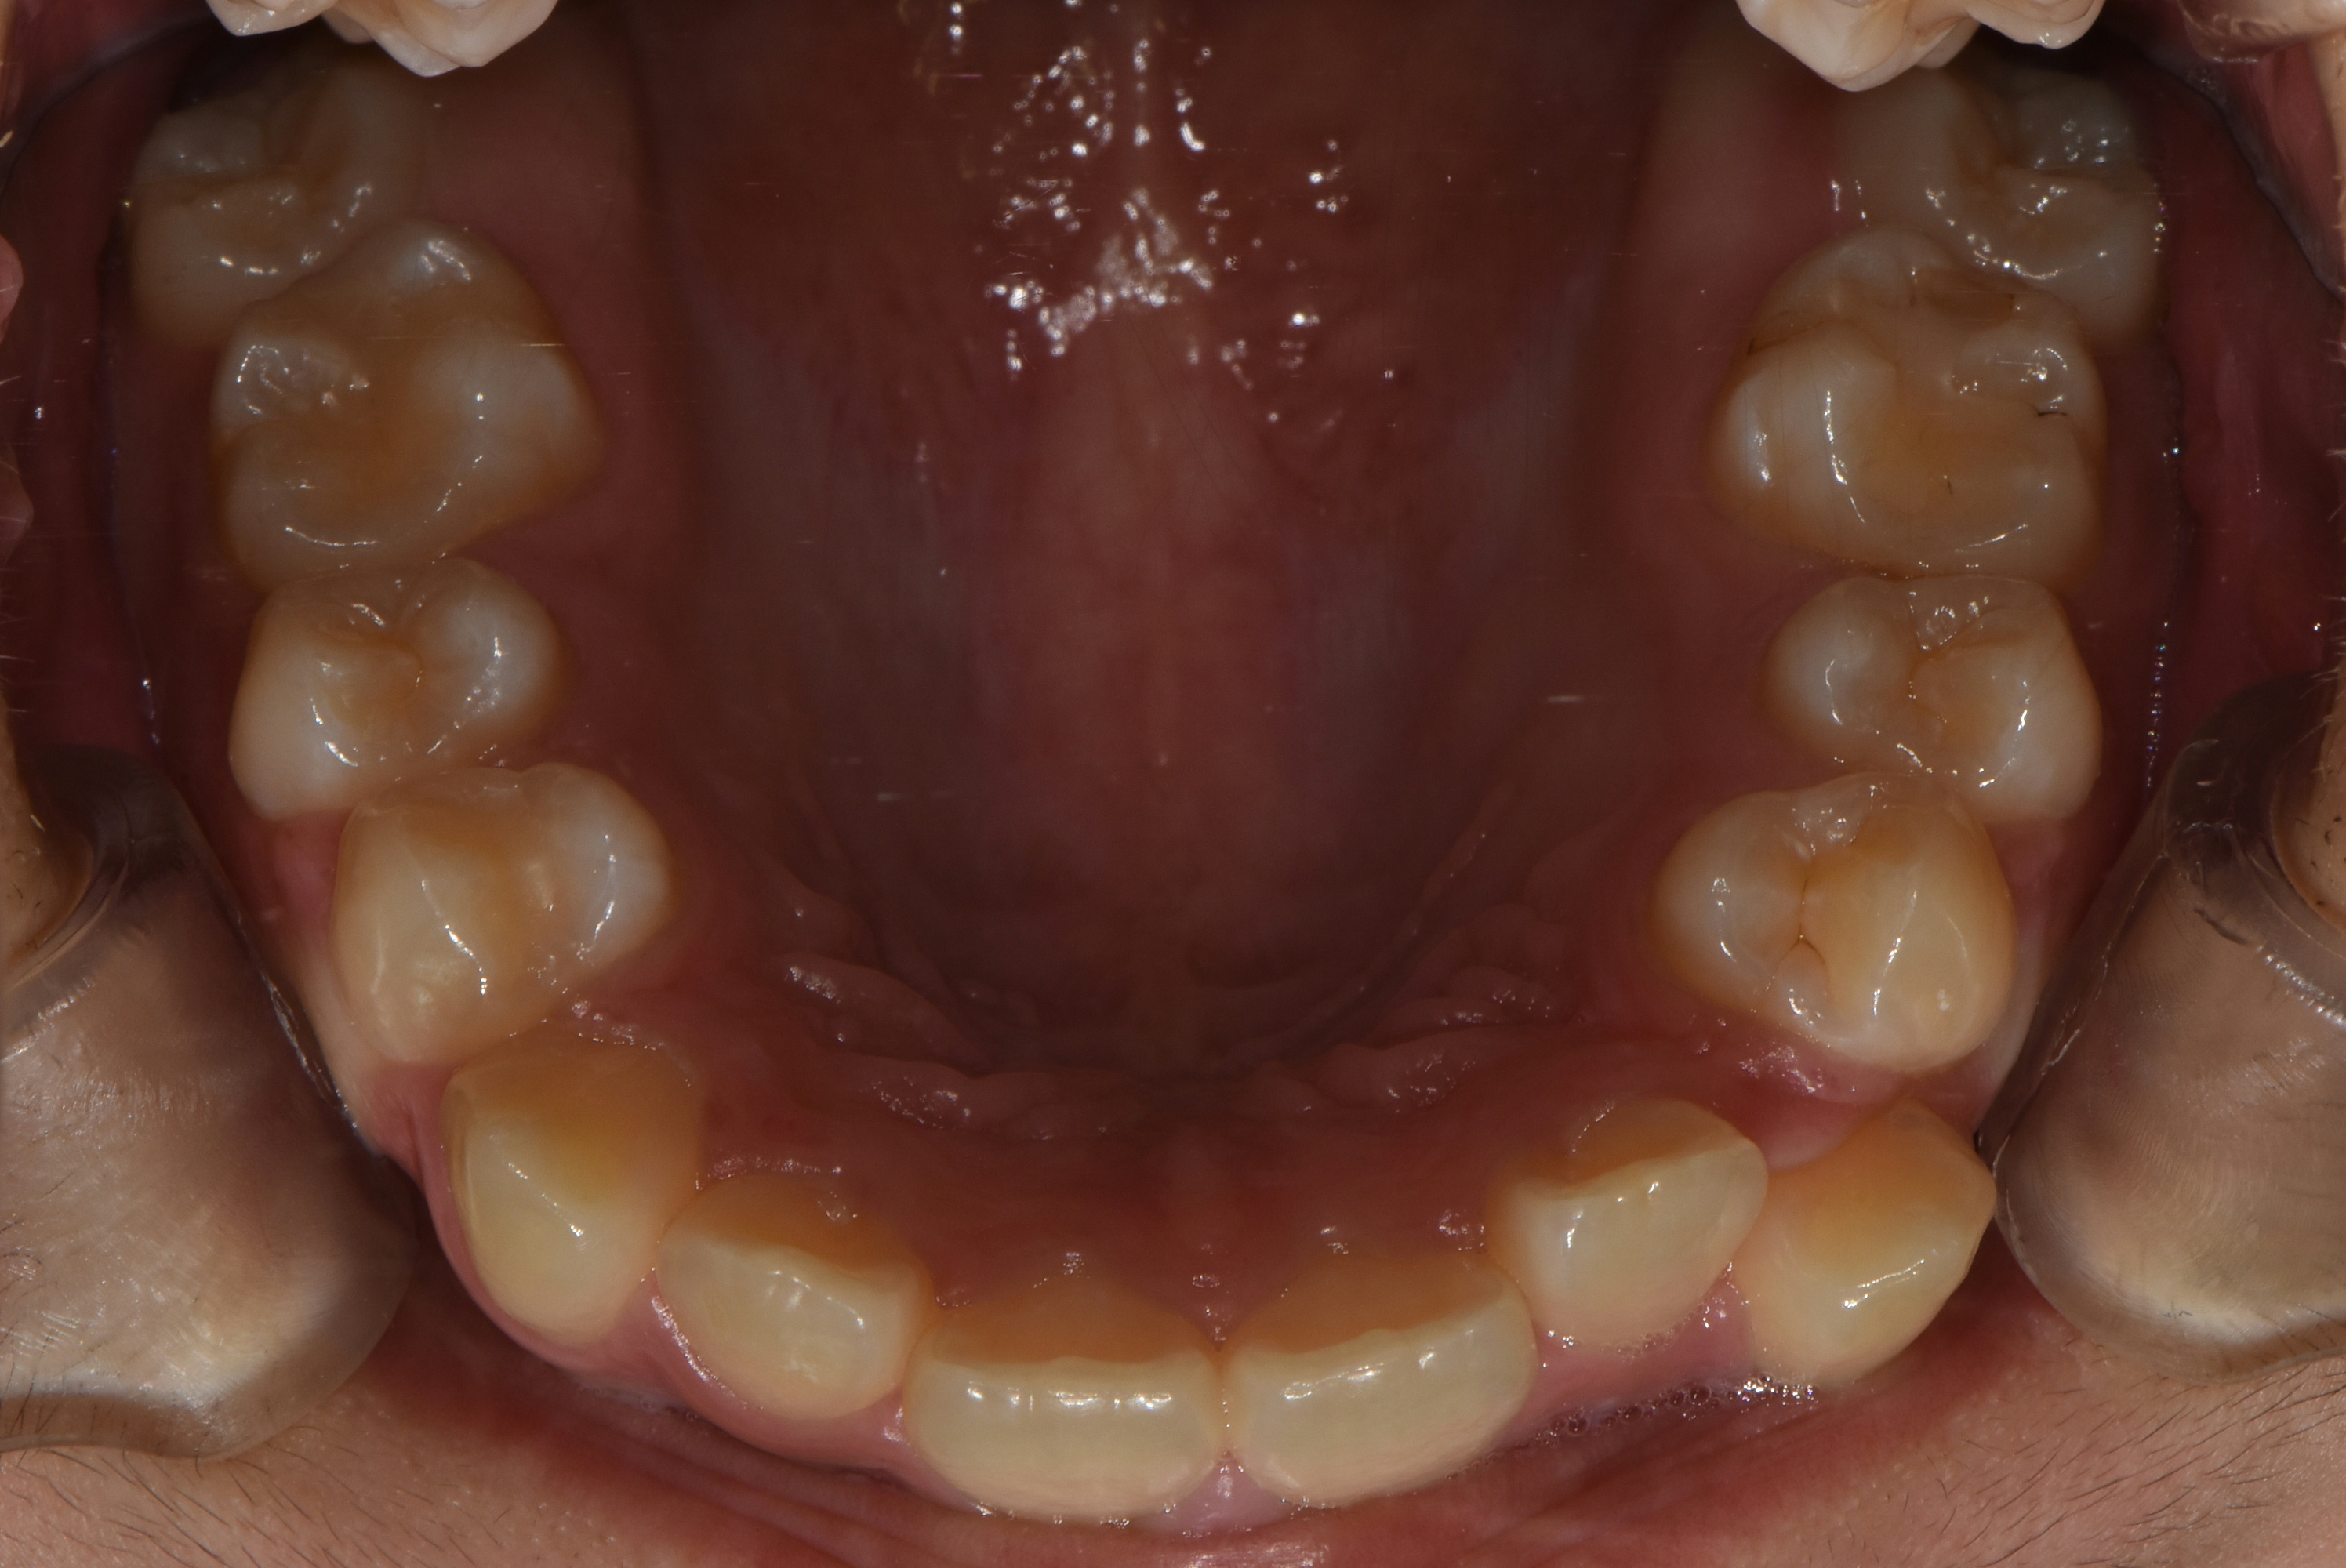

치료 후 사진입니다.